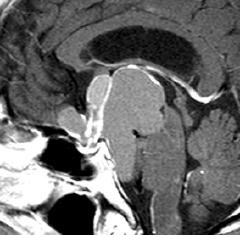

ちょっと大きな頭蓋咽頭腫です

嚢胞(液体が入っている袋)の部分と,腫瘍細胞が固まっている実質部分が入り交じっています。このくらいの大きさになってしまうと,下垂体機能を残すことはとても難しくなります。視神経が圧迫されて視力低下と視野障害を生じます。第3脳室が腫瘍で閉塞していて水頭症になっていますから知能の活動が低下します。

腫瘍を摘出するのに危ないのは,脳の血管の損傷です。左では白く,右では黒く線状に移っているのが太い脳動脈です。これら以外にもたくさんの細い重要な動脈が絡んでいます。

幸いこの患者さんの腫瘍は摘出できて患者さんは元気になりました。でもこのくらいのサイズになると手術がいつもうまくいくとは限りませんし重大な障害が残ることもあります。